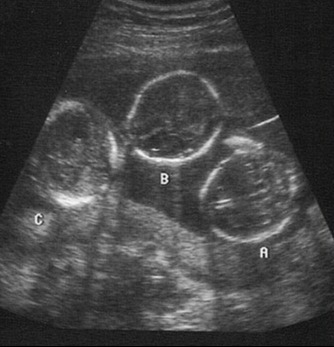

Lehetetlennek tűnt. Azonban tudjuk, hogy az élet nagy meglepetéseket tud okozni. Ebben az esetben is ez történt. A 42 éves Kimberly Fugate hármas ikrekkel lett terhes....